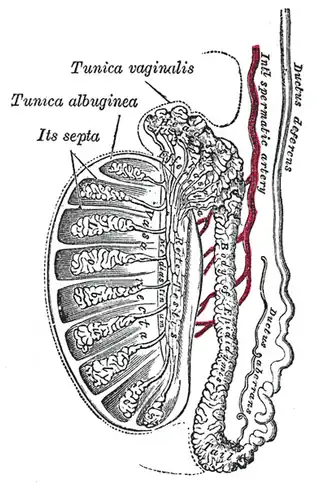

Seção vertical do testículo, para mostrar o arranjo dos dutos.

Seção vertical do testículo, para mostrar o arranjo dos dutos. -